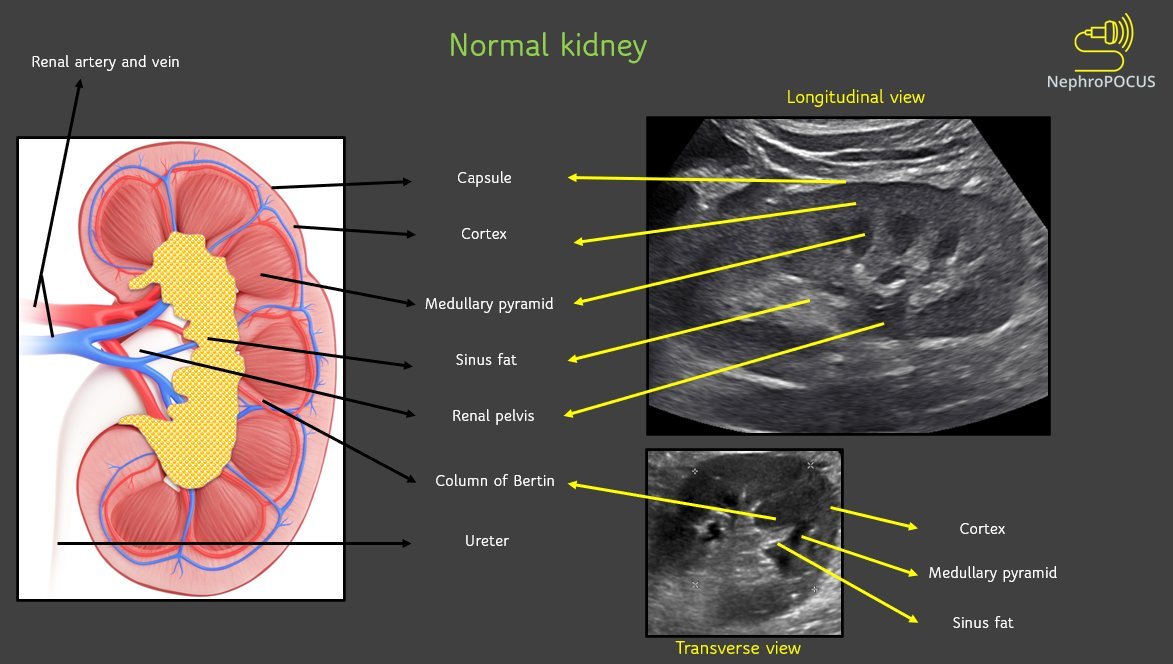

NephroPOCUS (@nephrop) 's Twitter Profile Photo

Simplistic representation of Pathophysiology of #cardiorenal disease. Do not ignore the venous congestion component. Use #VExUS #POCUS to gather objective data. #MedEd #Nephrology 🔗ahajournals.org/doi/10.1161/ci…

Simplistic representation of Pathophysiology of #cardiorenal disease.

Do not ignore the venous congestion component. Use #VExUS #POCUS to gather objective data.

#MedEd #Nephrology

🔗ahajournals.org/doi/10.1161/ci…